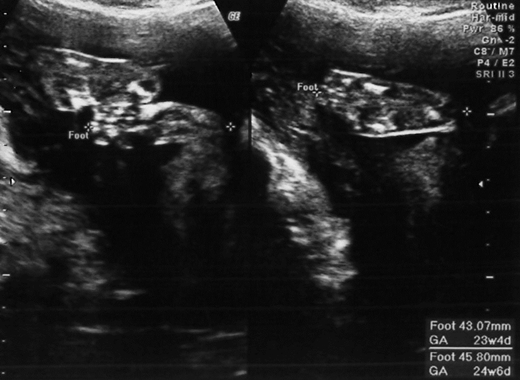

[孕事2] 20W‧高層次超音波

終於要去做高層次超音波囉!

這次高層次也是在中山杏群找舒醫生做的,費用是$3000元 (記得去年好像才$2500)

上舒醫師的課~不~~是給舒醫師做超音波真的超有趣的

除了很仔細的檢查每一個器官外,還會說很多鼓勵寶寶的話

看了活潑亂跳的小龍包,真的很可愛耶!

舒醫生說他有大眼眶,有大大的眼睛,尖尖的下巴,偶爾還會把腳腳放在嘴巴裡咬

但我有胎盤偏右的情形,到懷孕後期,小龍包可能會吸收不多的養份,長的比較小

其他的小龍包都長的很健康,還有大大的腳丫丫,希望他跟姐姐一樣可愛!!!

►寶寶長的健康,就是上天賜給我們最美好的禮物了! 舒醫生說有的寶寶照出來不健康,就必須終止妊娠,有的媽媽當場哭了出來,真的要很慶幸,小龍包長的很好,很健康! 我真的很幸運!

►照高層次超音波時,預測小龍包的預產期是11/25,現在想想真的很準耶!